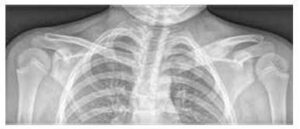

The most commonly affected bones are the metaphyses of long bones, the clavicle, vertebral bodies and pelvis (see Figure 2). The number of bone lesions varies (sometimes only a single lesion, more often multiple lesions). Sometimes, even asymptomatic lesions are revealed by bone scintigraphy or whole-body magnetic resonance imaging (WB MRI).

The basic examination is a native X-ray of symptomatic areas (see Figure 3), supplemented by magnetic resonance imaging and/or computed tomography.

Image No. 2

Comparison of bone lesion distribution on MRI in children with CRMO and septic osteomyelitis (according to Schnabel et al., 2016)

Image No. 3

Enlargement and osteolytic lesions of the medial end of the left clavicle and soft tissue oedema on X-ray